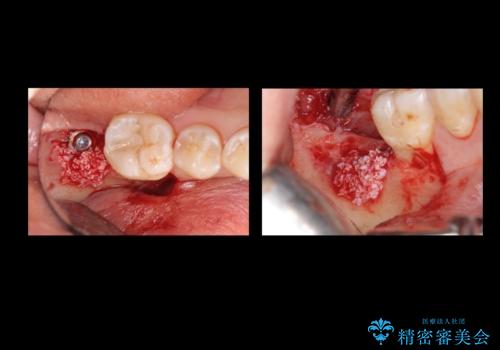

抜歯を行い、インプラントを入れていきました。

炎症で骨が少なかった場所には骨補填材を置いています。

高さがないため、スクリューリテインのインプラントの上部構造にしています。